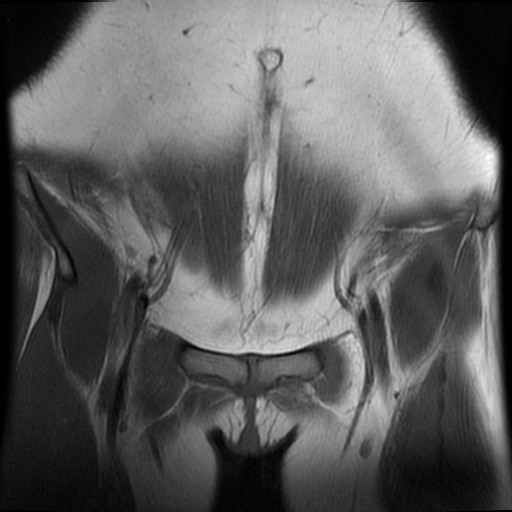

bekken